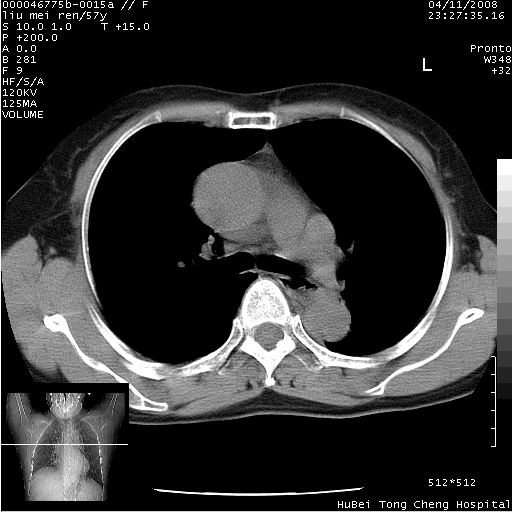

患者 女,57岁。因车祸受伤,其家属要求行“全身ct检查”。平素健康。

胸部ct轴位平扫(层厚10mm,螺距1.5,重建间隔10mm),图像如下:

左位上腔静脉,先天变异。

左位上腔静脉,先天变异。与双侧上腔静脉区别。